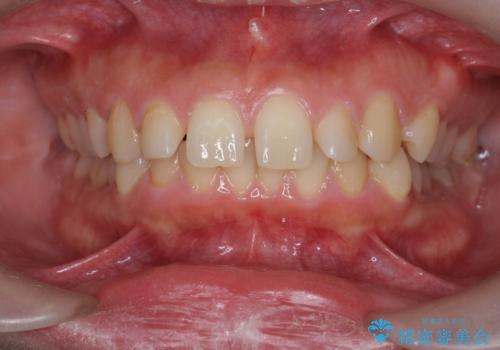

- 前歯のねじれ、深い噛み合わせ(ディープバイト)の改善を求めて来院されました。

マウスピースでは改善の難しい、歯のねじれ・ディープバイトを部分ワイヤー矯正で改善したのち、マウスピース矯正で全体の歯並びを整えていきます。

部分ワイヤー矯正を行ったことで前歯をしっかりと綺麗な歯並びへと導くことができました。